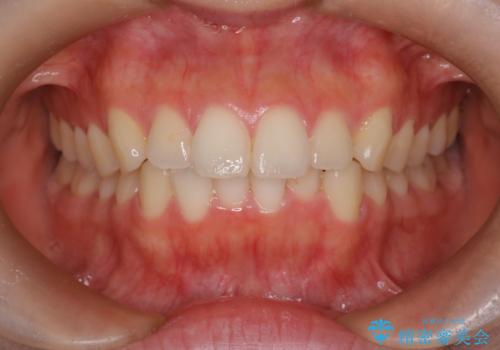

【インビザライン】前歯を下げたい

- 前歯が出ていることを主訴に来院されました。

奥歯を後ろに動かしながらスペースを作ることで、前歯を下げることができ患者さんにも満足していただきました。